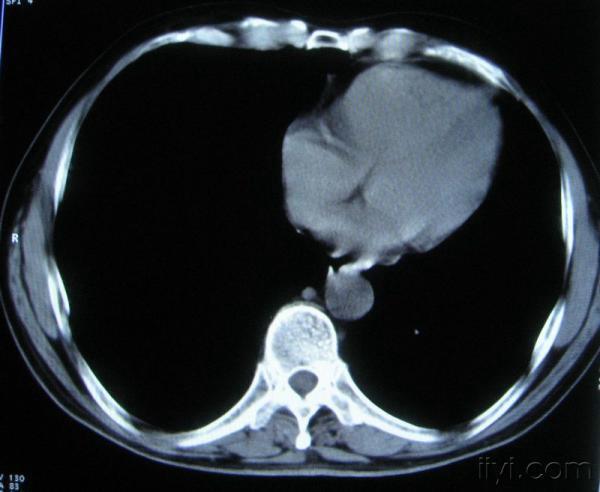

男。60岁,胸片示支气管炎治疗后复查CT。

应该是淋巴结没问题的,中心液化坏死是有这种情况的~~胸科常见到

你指那个肯定是淋巴结,中央系坏死,这很常见,特别在双侧腹股沟会经常看到。这个双侧腋窝及纵隔见多发小淋巴结征。

根据位置考虑应该是淋巴结,密度不均,是因为肿大的淋巴结中心液化坏死